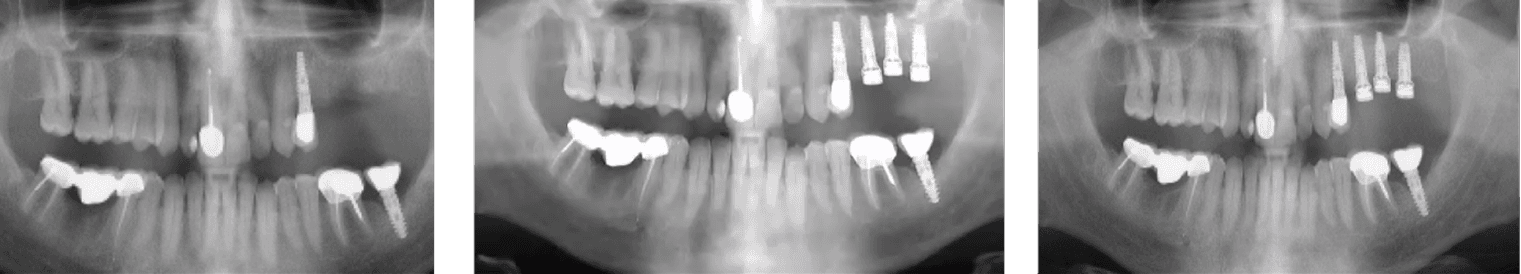

A patient presented with inflammatory environment and advanced crestal bone loss approximately five years after initial implantation. Clinical and radiographic evaluation revealed significant vertical bone resorption and signs of chronic inflammation around the affected implant. A non-surgical regenerative protocol was implemented, involving removal of the existing crown, thorough deep curettage and debridement of the infected tissue, and the placement of a MED healing abutment to promote localized bone regeneration and anti-inflammatory activity through pulsed electromagnetic stimulation.

Radiographic follow-up demonstrated a clear and progressive improvement in bone density and height.

• At 1 month, inflammation subsided with visible initial bone fill at the defect site.

• At 3 months, substantial vertical bone regeneration was observed, restoring crestal bone continuity.

• At 24 months, the regenerated bone remained stable, with a 3.7 mm gain in bone height, healthy peri-implant soft tissue, and no recurrence of inflammation or pocketing.

This long-term outcome highlights the regenerative and stabilizing potential of the MED healing abutment as an adjunctive therapy in managing inflammatory environment, even in chronic cases where conventional non-surgical methods typically show limited success. The treatment achieved full functional and esthetic rehabilitation with long-term peri-implant health and radiographically stable bone architecture.

A 55-year-old healthy patient presented with inflammatory environment approximately seven years after successful implant placement. Radiographic evaluation revealed significant vertical bone loss around the implant, indicating advanced peri-implant bone resorption. A non-surgical regenerative protocol was initiated, consisting of removal of the prosthetic crown, deep mechanical debridement and curettage of the infected site, followed by the application of a MED healing abutment to stimulate local bone regeneration and reduce inflammation.

After only one month, radiographs demonstrated clear evidence of vertical bone regeneration around the affected implant, with visible bone fill in previously resorbed areas. The peri-implant tissue exhibited healthy tone and stability, with no bleeding or signs of inflammation. The regeneration process successfully preserved the implant, avoiding the need for complex surgical intervention or implant replacement. This case highlights the role of MED technology as an effective adjunctive treatment in the non-surgical management of inflammatory environment, promoting rapid bone healing and long-term implant stabilit

A 70-year-old healthy patient presented with inflammatory environment and advanced vertical bone loss around two adjacent implants supporting a fixed bridge. The treatment protocol included removal of the prosthetic bridge, thorough non-surgical debridement and deep curettage of the affected sites, followed by the application of MED healing abutments to promote bone regeneration and reduce inflammation through localized electromagnetic stimulation.

Within three months, radiographic evaluation revealed substantial vertical bone regeneration, effectively restoring nearly the entire height of the previously resorbed bone. Bone levels improved from 2.5 mm and 2.3 mm of loss at baseline to 1.2 mm and 2.0 mm of residual pockets, representing approximately 100% recovery of the lost bone height. The regenerated bone exhibited dense, well-integrated structure, and the peri-implant tissue remained healthy with no recurrent inflammation.

• This case demonstrates the regenerative capability of MED healing abutments in reversing peri-implant bone loss and achieving implant preservation through a predictable, minimally invasive, and non-surgical approach.